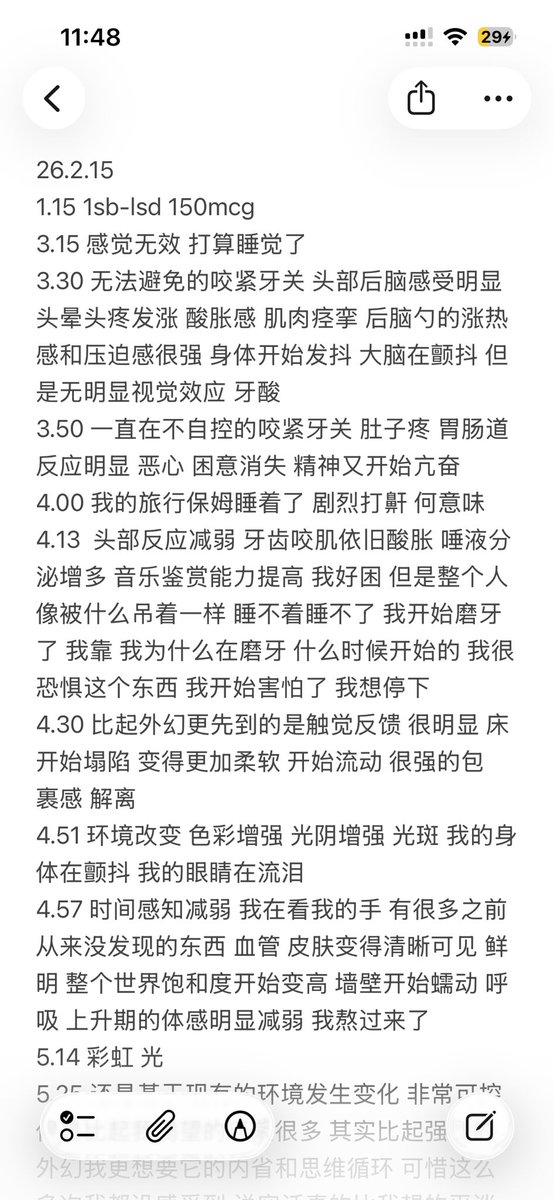

一些白兔27t的体验:

显著的梦境增强,几乎是半梦半醒的状态(或许是咖啡因导致的?),会梦到很多开心的事态发展并相信那就是事实,虽然在6h的睡眠后醒来不记得内容了(好希望能记住)

没有服用会干扰酶的药物或食物。

睡眠期间心率和血氧的数据比平时低一些。总之没有发生什么很特别的事。 https://t.co/PAXqkakGGo